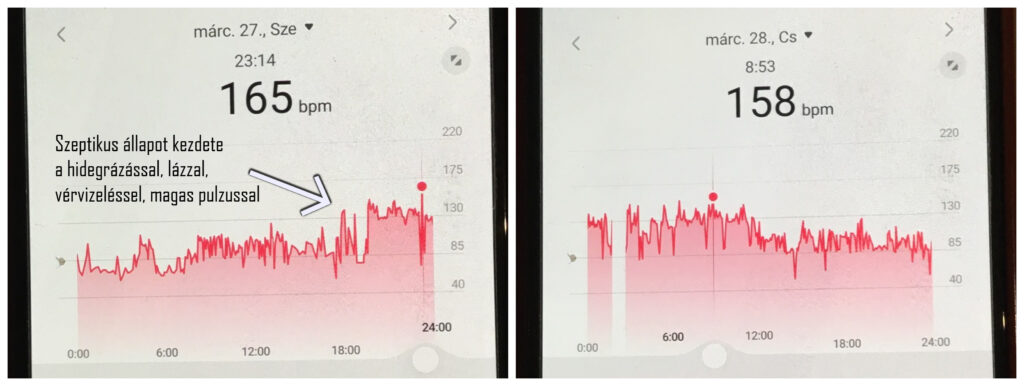

16./ Március 27. Tatabányai Szent Borbála Kórház, Urológia: Dr Csiki Csaba, majd SBO

Dr Csiki Csaba Ciprofloxacin antibiotikumot és CT urográfiát írt elő előjegyzéssel, azonnali kórházi felvételt nem. Külön megemlíteném, hogy a fiam ekkorra már – közel 2 hónap kezeletlenség után – olyan állapotban volt, hogy azt mondta a rendelés elején, hogy „úgy érzem, szepszist fogok kapni”.Az orvosnak kikerekedett a szeme, nem akarta elhinni, majd Zsolt elmondta mi történik körülötte 2 hónapja, aki ennek ellenére mégsem vette fel kórházi, intravénás kezelésre. És aznap este a fiam belázasodott, hidegrázása és ismét véres vizelete lett, nagyon magas pulzussal! Bementünk a tatabányai kórház sürgősségijére, ahol elmondtuk – én és a fiam, sőt az apja is – hogy mi folyik vele 2 hónapja, és milyen tünetei vannak. Minden előzményt is. Ebből tudnia kellett volna annak, aki az ablaknál volt, hogy vérmérgezés gyanús beteg érkezett és elrendelni az azonnali kivizsgálását. Ehhez képest Zsoltot visszahívták az ablak mögé, hogy mondja el ugyanazt amit 5 perce, most egy másik nőnek. A fiam megint elmondott mindent, miközben mértek egy lázat és pulzust nála.

Ezután azt mondták üljön le a váróban. Az idő telt, nem történt semmi, nagyon szenvedett, míg kb 1 óra elteltével megkérdezte tőle egy nővér, „magát még senki nem látta?” – Nem – mondta a fiam. Eltelt pár perc, Zsolt felállt és az arra jövő férfi kollégának mondta, hogy „nem akar szepszist kapni, nagyon rosszul van!”. Ez a férfi kolléga, akiről kiderült hogy a tatabányai mentőállomás vezetője, odamondta egy kolléganőnek ezt, aki gúnyosan kvázi kinevette ezt, majd flegmán mondta a fiamnak, „jöjjön be ide.” Ami egy orvosi vizsgáló volt, de mint kiderült, amit akkor még Zsolt nem tudott, ez csak egy mentőápoló nő volt, orvos még mindig nem látta. Normális egészségügyi dolgozó helyett olyanokat mondott a fiamnak, hogy „Nyugodjon le, ne rázza a lábát, ne idegeskedjen…” „De nem érdekelnek a leletek, nem érdekel semmi csak az, hogy mit mondtak az orvosok.” Na most gondolhatja mindenki, hogy ilyen szeptikus/preszeptikus állapotban mennyire van türelme egy betegnek az ilyen játszmákhoz… Zsolt ezt már nem viselte tovább, látta, hogy egyedül az ő neve mellett volt üres a „triázs” kijelző, semmit nem tudnak az előzményeiről, amit elmondott, vagy az EESZT-ből. Miközben legtöbbjük telefonozott vagy csak úgy üldögéltek a pultban – mint akiknek semmi dolguk nincs. Ekkor mondta hangosan a fiam, hogy elég volt a szórakozásból, nem fogják itt megölni azzal hogy nem csinálnak semmit, nyissák ki az ajtót – és kiment. A folyosón pedig kiabálva mondta, hogy mindenki hallja, hogy 2 hónapja jár több mint százszoros, ezerszeres vérvizeléssel, vesefájdalommal kórházról kórházra, már lázasan, hidegrázással és „itt hagyják megdögleni” – ugyanezt kiabálta az apja is. Valami ilyesmit mondott, majd mondta, hogy menjünk el innen.

Szörnyű, milyen állapotba juttatták a fiamat a vesekőzúzás (ESWL) utáni súlyos vesefertőzése kezeletlenségével! Robbanásszerű hasmenései (5-8 epizód), rengeteg vizelete (20-30 epizód), 100-140 körüli pulzusa, súlyos inszomniája és a tűrhetetlen vesefájdalommal együtt megjelenő, egyre erősödő baloldali mellkas,-hát és oldalfájdalma voltak. A kezeletlenségtől vérmérgezést kapott. Kilábalt belőle, de a tünetei máig olyanok, mint betegsége elején.